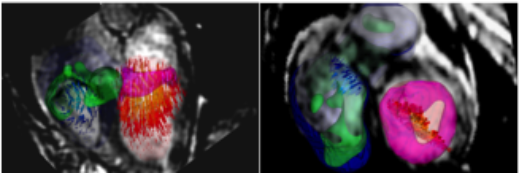

Del Alamo Lab@delAlamoLab·19 KasMeasuring cell-cell forces in beating cardiomyocyte cultures sciencedirect.com/science/MiamiM…Çevir English0010

Del Alamo Lab@delAlamoLab·19 KasCyclic stretch of embryonic cardiomyocytes increases proliferation, growth, and cell-cell forces! sciencedirect.com/science/articl…Çevir English0010